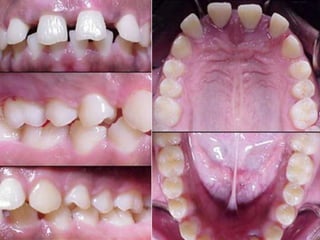

Age of onset is around puberty

Localized involvement of 1st molar/incisor

Interproximal attachment loss on atleast two

permanent teeth, one of which is a 1st molar

Involves no more than two teeth other than 1st

molar & incisors

Distolabial migration of maxillary incisors with

concomitant diastema formation

Increase mobility of first molars

Age of onsetis around puberty Localized involvement of 1st molar/incisor Interproximal attachment loss on atleast two permanent teeth, one of which is a 1st molar Involves no more than two teeth other than 1st molar & incisors Distolabial migration of maxillary incisors with concomitant diastema formation Increase mobility of first molars Sensitivity of denuded root surfaces to thermal & tactile stimuli. Deep,dull,radiating pain during mastication,probably caused by irritation of the supporting structures by mobile teeth & impacted food Periodontal abscess may form at this stage & regional lymph node enlargement may occur.